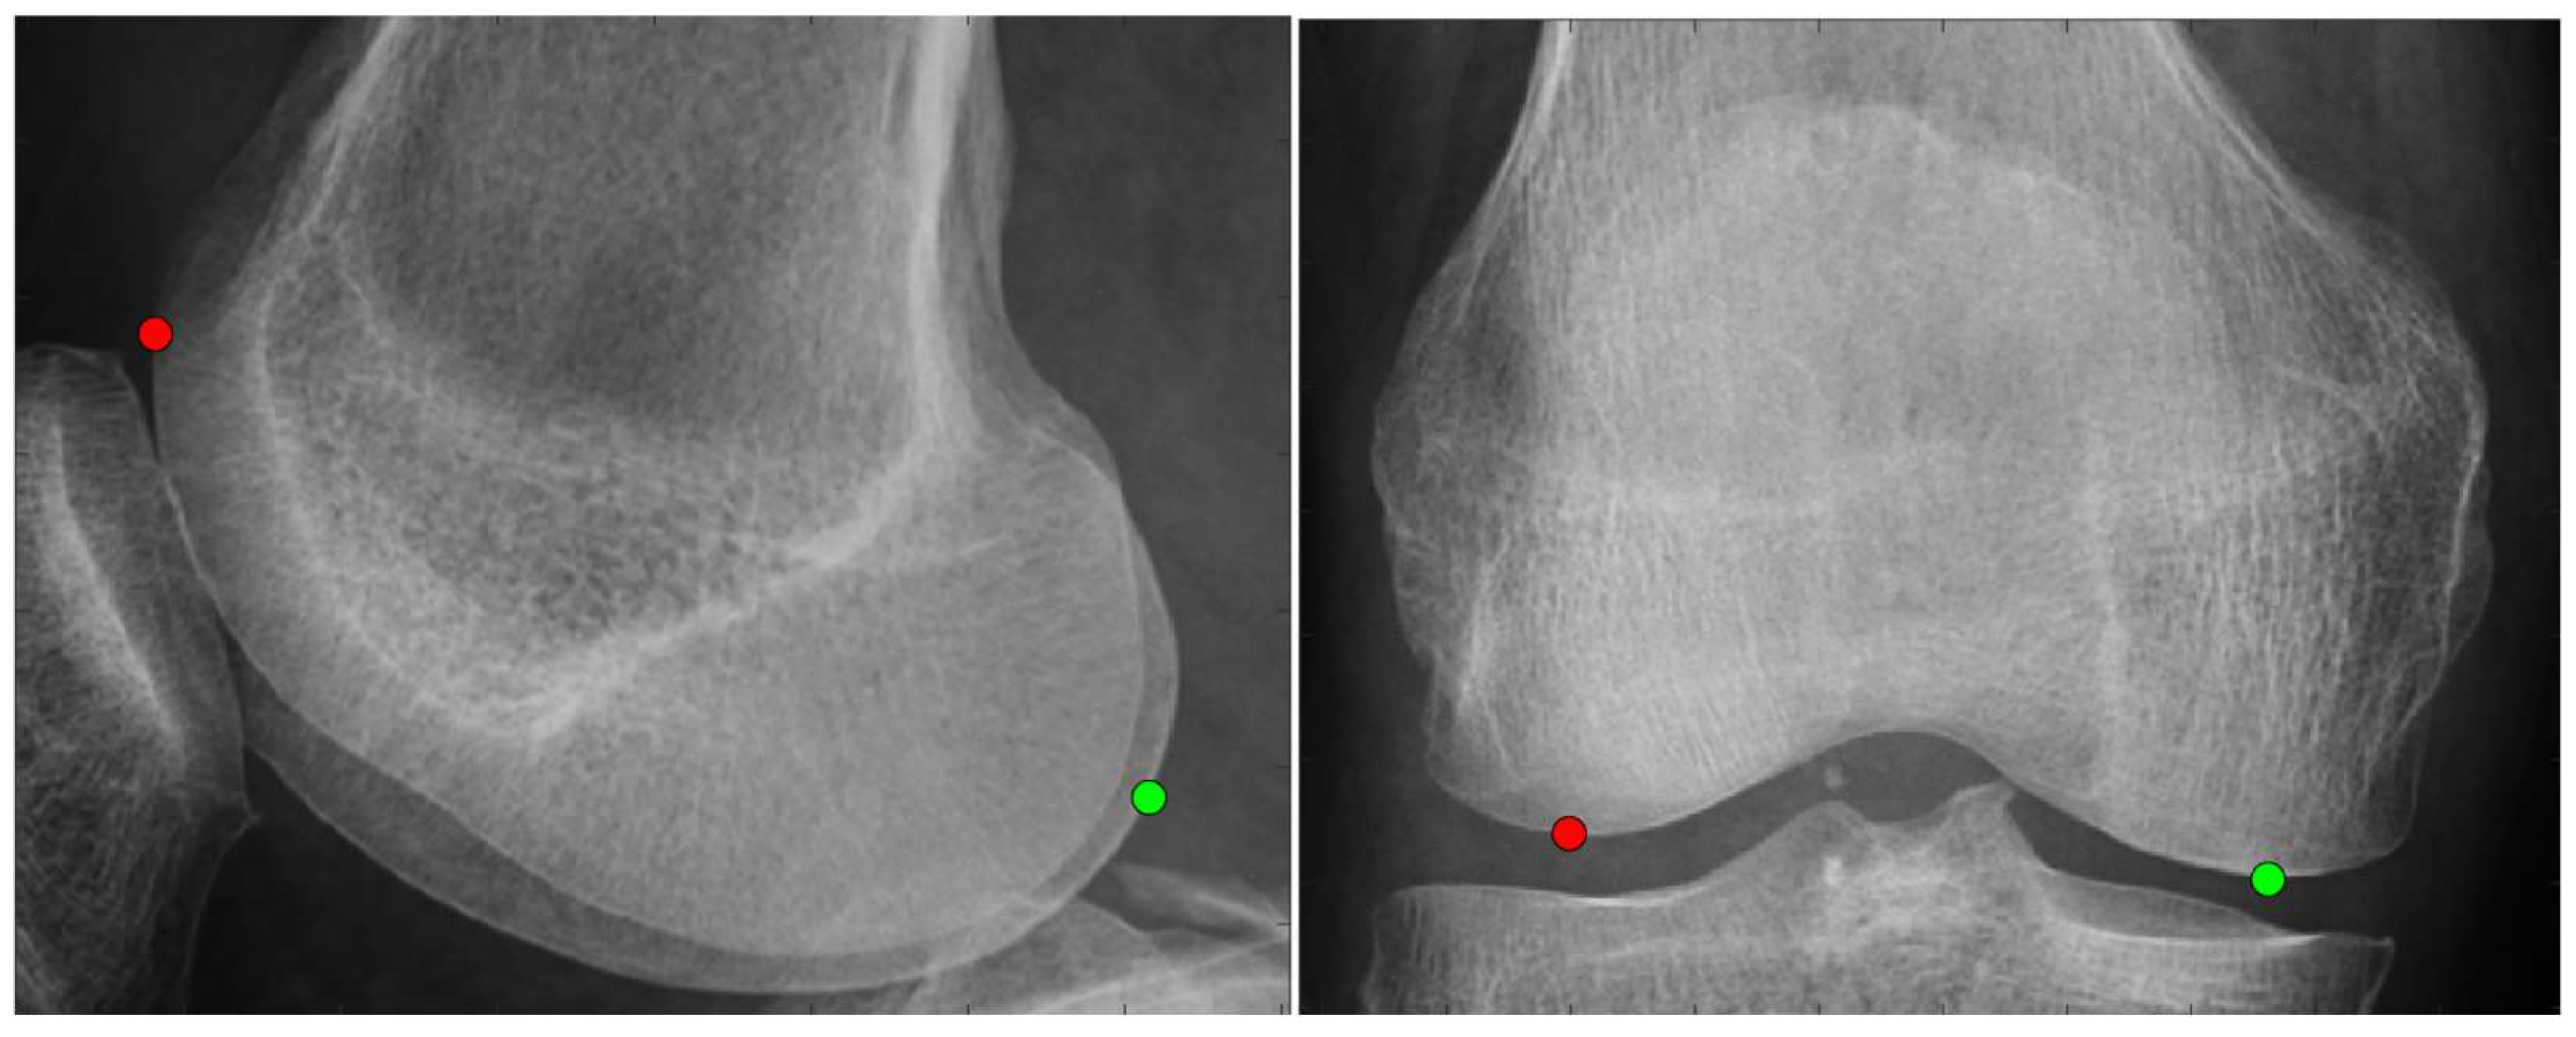

2.3.1. Anatomical Feature Point

2.3.2. Scanning Feature Values

- Select two points located at both ends.

- Of the two points obtained in step 1, designate the point located posteriorly in the sagittal plane and laterally in the coronal plane as the reference point.

- Draw a perpendicular line on the images that divides the two points into n equal parts.

- Obtain the intersection of the line drawn in step 3 and the bone contour line.

- Calculate the distances between all points and the reference point and use them as the feature values.